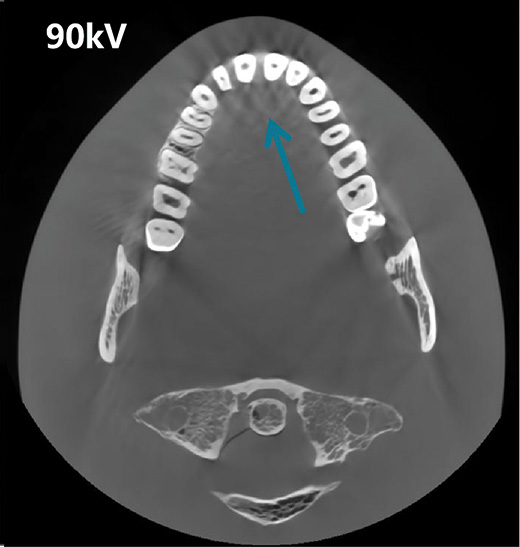

Reducción de Artefactos Metálicos (MAR)

Imagenes de Dosis Baja Impulsadas por IA

Reduccion de Ruido y Correccion de Endurecimiento del Haz

Corrección Geométrica

Algoritmo de Corrección de Movimiento (PMC)

Reconstrucción Panorámica Multicapa